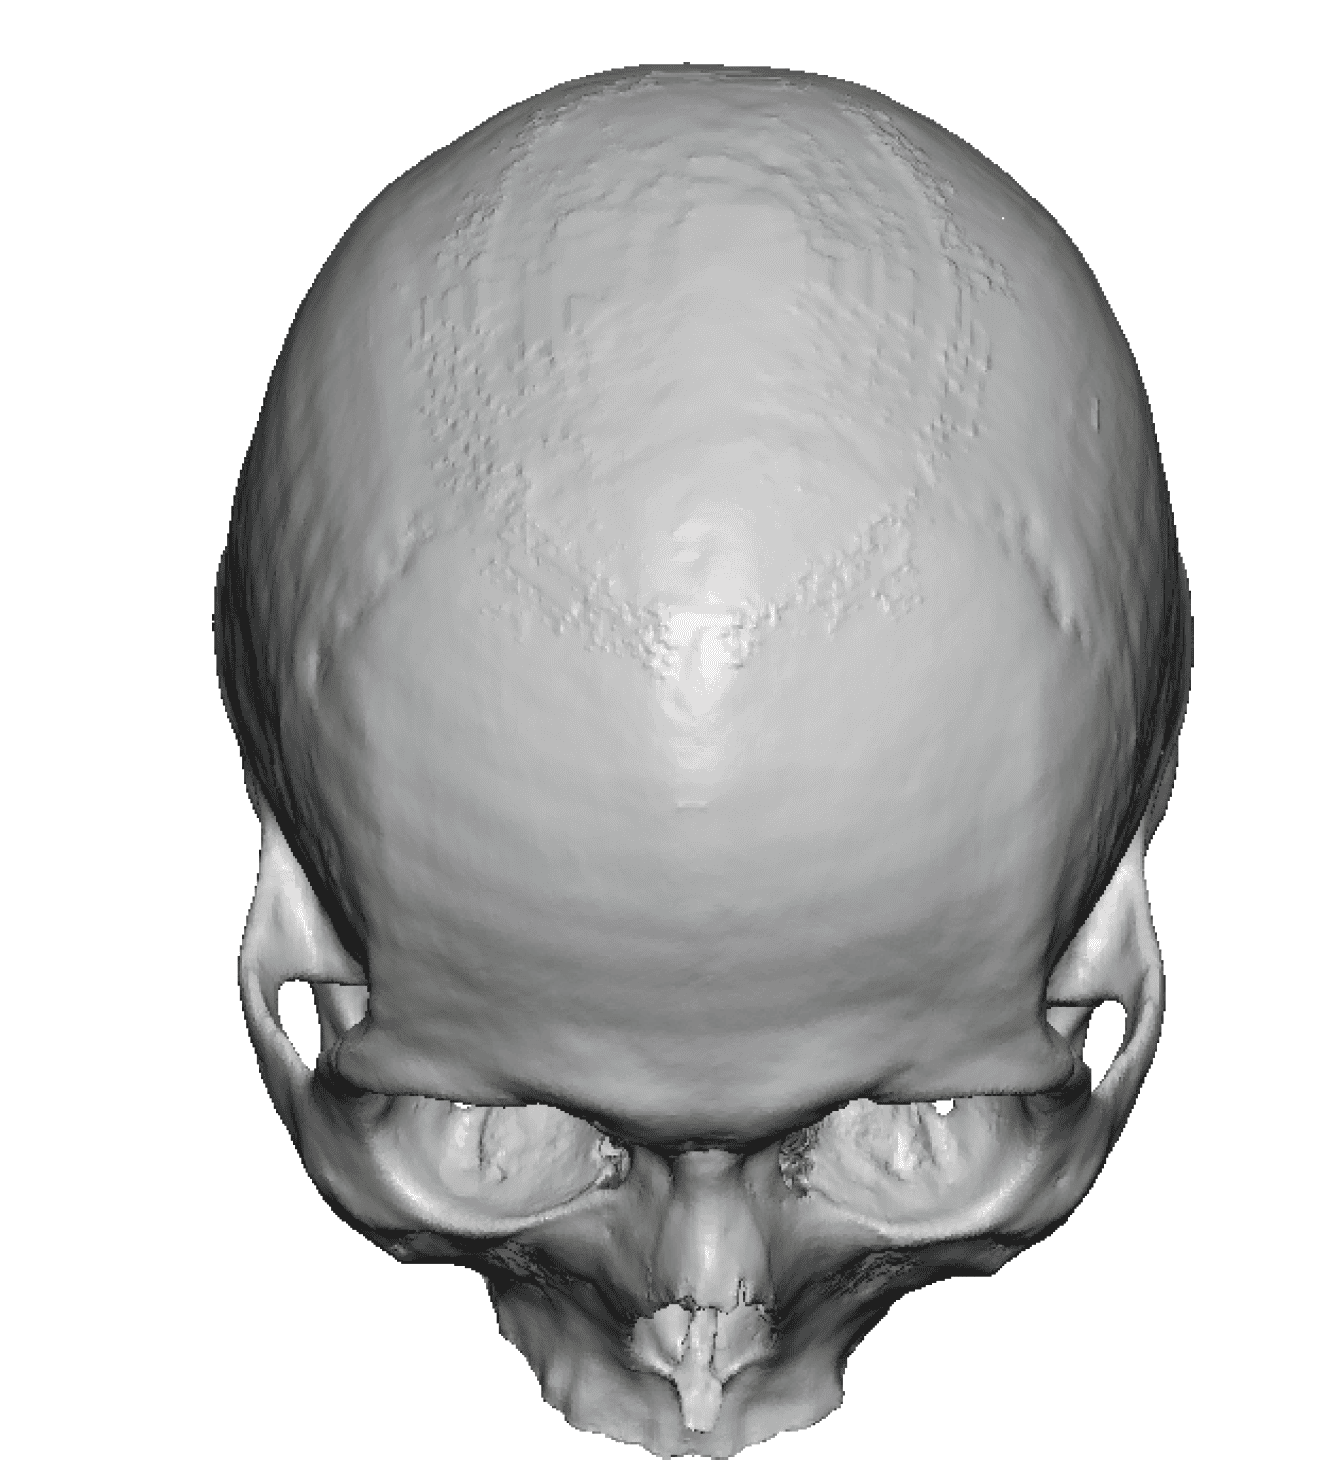

Patient 28

Desire for rounder shape to the top of the head from a congenital parasagittal deficiency skull shape.

Custom skull implant designed to fill in the parasagittal deficiencies.

Desire for rounder shape to the top of the head from a congenital parasagittal deficiency skull shape.

Custom skull implant designed to fill in the parasagittal deficiencies.